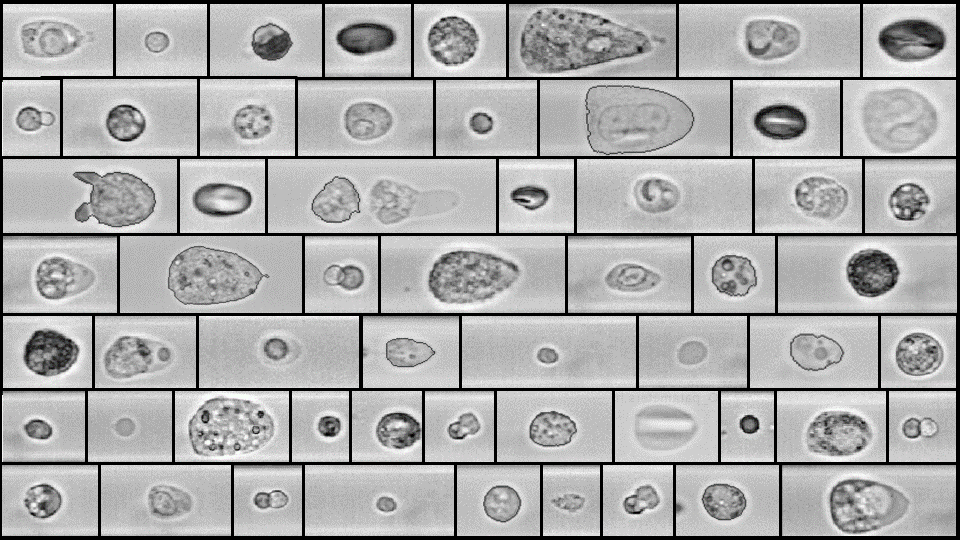

Blutuntersuchung und Erkennung von Erregern

Klassifikation ist ein Verfahren des überwachten maschinellen Lernens, bei dem Daten bestimmten, vorher bekannten Klassen zugeordnet werden. Ziel ist es, ein Modell zu trainieren, das anhand von Merkmalen erkennt, zu welcher Kategorie ein neuer Datenpunkt gehört. In der Bildanalyse wird Klassifikation häufig eingesetzt, um Objekte wie Pflanzen, Gebäude oder Landschaftsformen automatisch zu erkennen und zu unterscheiden.

Die gezeigten Bilder veranschaulichen diesen Prozess anhand von Baumarten. In den oberen Darstellungen sind abstrahierte Formen einzelner Bäume zu sehen, die typische Merkmale wie Kronenstruktur oder Umriss zeigen. Diese Merkmale dienen dem Modell als Grundlage, um Unterschiede zwischen Baumarten zu lernen. Die mittleren Bilder zeigen farbige Luftaufnahmen, in denen verschiedene Vegetationstypen sichtbar sind. Hier spielen Farbton, Textur und Flächenausdehnung eine Rolle bei der Unterscheidung.

Im unteren Bereich wird das Ergebnis der Klassifikation auf einer Karte dargestellt. Jeder Punkt steht für einen erkannten Baum, und die farblich markierten Flächen zeigen die Umgebung, etwa Wasserflächen oder bewachsene Gebiete. Die Zuordnung von Baumarten erfolgt auf Basis der zuvor gelernten Merkmale, sodass das Modell auch in neuen Gebieten automatisch erkennen kann, welche Baumart vorliegt.

Klassifikation ist besonders nützlich, wenn große Mengen an Bilddaten effizient ausgewertet werden sollen. In der Umweltforschung, Forstwirtschaft oder Stadtplanung hilft sie dabei, Informationen zu gewinnen, die sonst nur durch manuelle Analyse zugänglich wären.